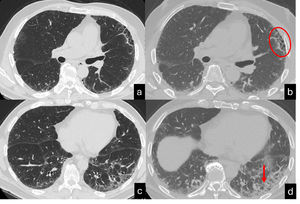

Evans et al. postulated that excessive production of MUC5B by stem cells that attempt to regenerate injured bronchiolar and alveolar epithelia may disrupt normal developmental pathways and enhance normal reparative mechanisms in the distal lung.113 This was recently demonstrated by histological, CT, and micro-CT analyses of eight explanted lungs or lobes with ILAs from six donors.124 The authors drew a correlation between the findings of ex vivo CT scans and the histological samples, reporting scarcely affected or near-to-normal portions of parenchyma with paraseptal fibrosis in most cases (78 %) and lymphocytic inflammation (86 %). Of particular interest is the concept of ‘paraseptal’ fibrosis, which has been described to originate from the periphery of the secondary lobule and moving inward to the centrolobule. This has already been described in surgical specimens by Colby et al. and, more recently, by Johkoh et al.140,141 The early changes in UIP patterns are characterised by an admixture of dilatation of the terminal airway and periacinar fibrosis. The peripheral acinar distribution is typical of the less fibrotic areas and can be discerned as emanating from the septa and the pleura around the bronchovascular structures.140 The corresponding imaging aspect is the reticulation, which assumes an ‘arciform aspect’ when it is subpleural or is polygonal shaped when it is far from the pleura (Fig. 6). This periacinar pattern may be identifiable in transbronchial cryobiopsy samples (Fig. 7a,b). The periacinar distribution may still be discernible on follow-up CT scans even when a typical UIP pattern appears (Fig. 7c,d). Verleden et al. also found that the opacities in or near the interlobular septa are thicker and, in more advanced stages, associated with aberrant airway-like structures that gradually fill the entire secondary lobule with progressive loss of alveolar epithelium.124 A UIP-like pattern has been described in association with pleuroparenchymal fibroelastosis (PPFE), which shows a clearly worse prognosis in comparison with other phenotypes of PPFE.142,128 While elastin fibres in the normal lung contribute to normal lung compliance and elastic return, in ILDs, overexpression of elastin leads to scarring and impaired lung function.129 An increased elastin burden has been documented in the proliferative phase of DAD and in UP as well, suggesting that it may contribute to the alveolar mechanical dysfunction and remodelling both in acute and chronic ILDs.130 In the UIP pattern, the elastin deposition is observed along the interalveolar and alveolar septal wall, and its degree correlates with the disease progression and 5-year survival.131 PPFE is also one of the most representative findings in telomere diseases, being part of a constellation of atypical or discordant findings on pathological and radiological assessments.132 The future horizons of imaging are represented by a further improvements in the resolution and the identification of coarseness. Ultra-high-resolution photon-counting CT allows more precise depiction of the lung parenchyma, with a sharper delineation of the subtle features of nonfibrotic and fibrotic ILDs.133 Finally, the implementation of deep learning algorithms for assessment of IPF represents an emerging tool that may address several unmet needs both in the research setting and in clinical practice.134,143

CT scan (a,b) shows reticulation associated with mild architectura lobular distortion, visible in the peripheral lung. This finding assumes an «arciform aspect» beneath the pleura (yellow arrow) and a poligogonal shape in the inner parenchyma (yellow circle). Scattered pulmonary ossifications are also present bilaterally. Cryobiopsy (c): the interlobular septum (star) and the centrilobular zone (arrow) are identifiable. A tongue of fibrotic tissue with an arc-like shape connects these two anatomic zones (H&E, low power).